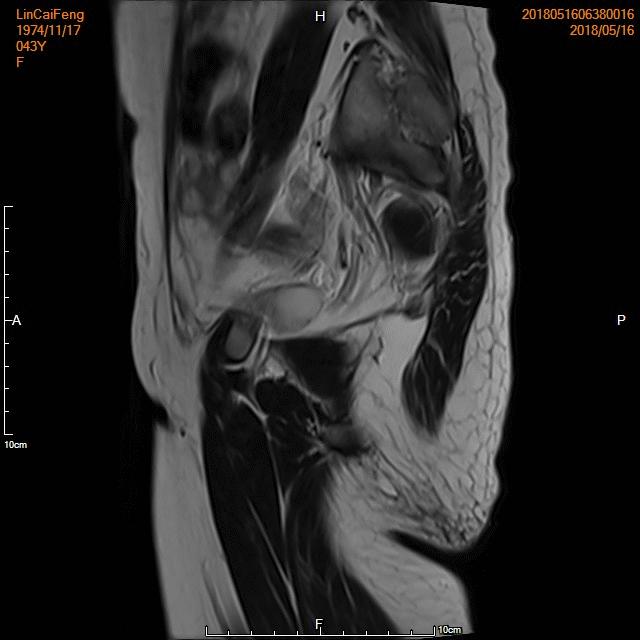

- 术前彩超、磁共振检查显示子宫明显增大,子宫前壁可见弥漫型子宫腺肌症病灶,合并粘膜下、肌壁间子宫肌瘤。

横断位

冠状位

矢状位